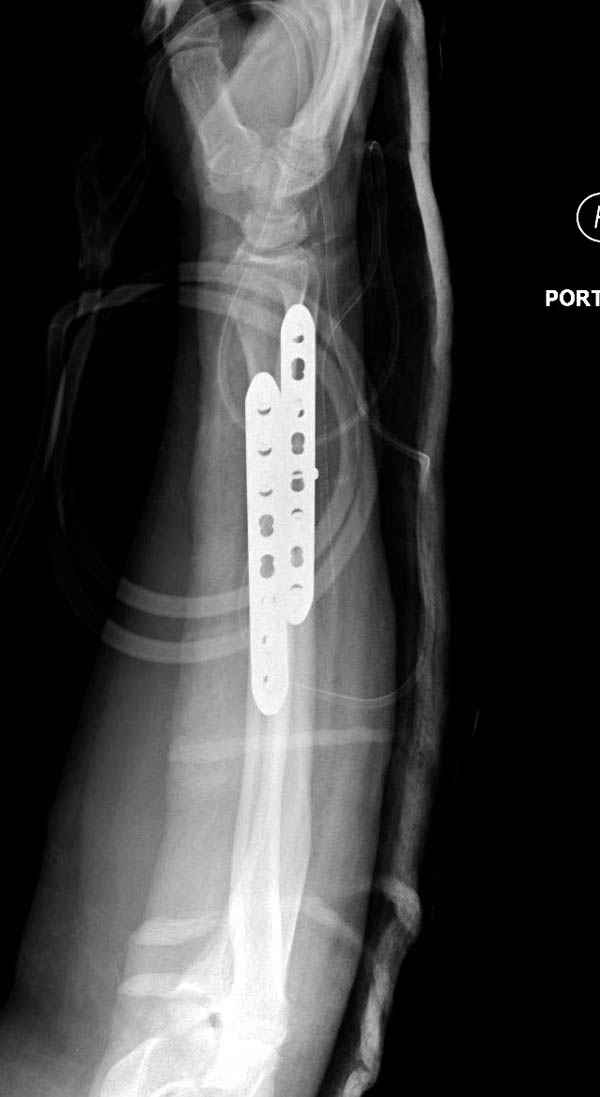

Второй случай, для лечения перелома проксимального

плеча применили пластину "Hand Innovation"

http://www.handinnovations.com/pdf/S3_technique.pdf

Пластина имеет преимущества перед другими "Locking

Implants", потому что пластину можно уложить намного ниже чем другие пластины и имеется возможности проведения шурупов под 130 градусным углом, таким образом можно уменьшить операционный разрез в проксимальной части.

Прооперирован вчера на 13 день после поступления.

Больному 41 и из-за гемодинамической нестабильности в течение первых 7 дней был в реанимации под интубационной седацией.

Кроме перелома плеча у больного старый дистракционный перелом T12-L1 оперированный когда-то и кем-то, открытый перелом костей предплечья, который был прооперирован в ночь поступления, после I&D (хирургической обработки). Из-за разрыва селезенки при поступлении травма хирургами произведено удаление.

Извиняюсь за качества снимков, обычный больной в 300 фунтов, портативным ренген аппаратом не пробить.